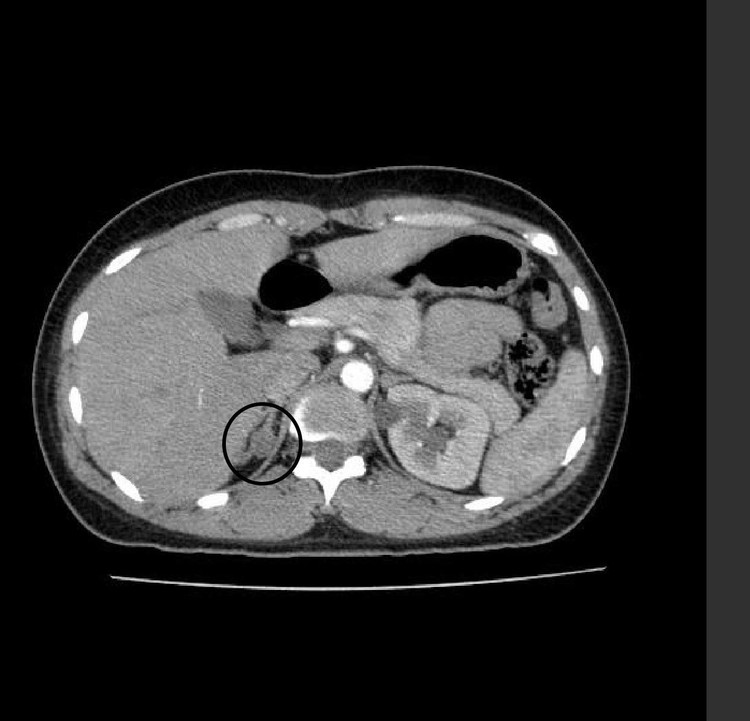

| Hình ảnh u trên phim chụp - Ảnh BVCC |

Gần đây xuất hiện triệu chứng co quắp tay chân kèm mệt mỏi, 2 tuần trước bệnh nhân đã đi khám phát hiện nguyên nhân là do có 1 khối u tuyến thượng thận phải.

Sau hội chẩn bệnh nhân được chỉ định phẫu thuật nội soi bóc đồng thời U vỏ tuyến thượng thận phải và u nang buồng trứng phải. Ca phẫu thuật diễn ra thành công, hiện tại sức khoẻ bệnh nhân đang hồi phục và ổn định trở lại.